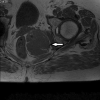

Aggressive angiomyxoma is a rare mesenchymal tumour, primarily arising in the soft tissue of the pelvis and perineum in women of reproductive age. There is a paucity of evidence on optimal management because of the rarity of these tumours, but the consensus has been for surgical excision. We present the case of a 65-year-old woman who was admitted with left-sided buttock pain and initially diagnosed with a perianal abscess. She underwent examination under anaesthesia rectum with surgical excision of the lesion, subsequent histopathological and immunochemical analysis was suggestive of aggressive angiomyxoma. To complement our case report, we also present a literature review focusing on aggressive angiomyxoma in the ischioanal fossa (also known as the ischiorectal fossa) with only eight cases of primary aggressive angiomyxoma involving the ischioanal fossa documented to date. The primary aims of this case report and literature review are to familiarise clinicians with the clinical, histopathological and immunochemical features of these tumours, and to increase appreciation that despite the rarity of aggressive angiomyxoma, it might be considered in the differential diagnosis of ischioanal lesions.